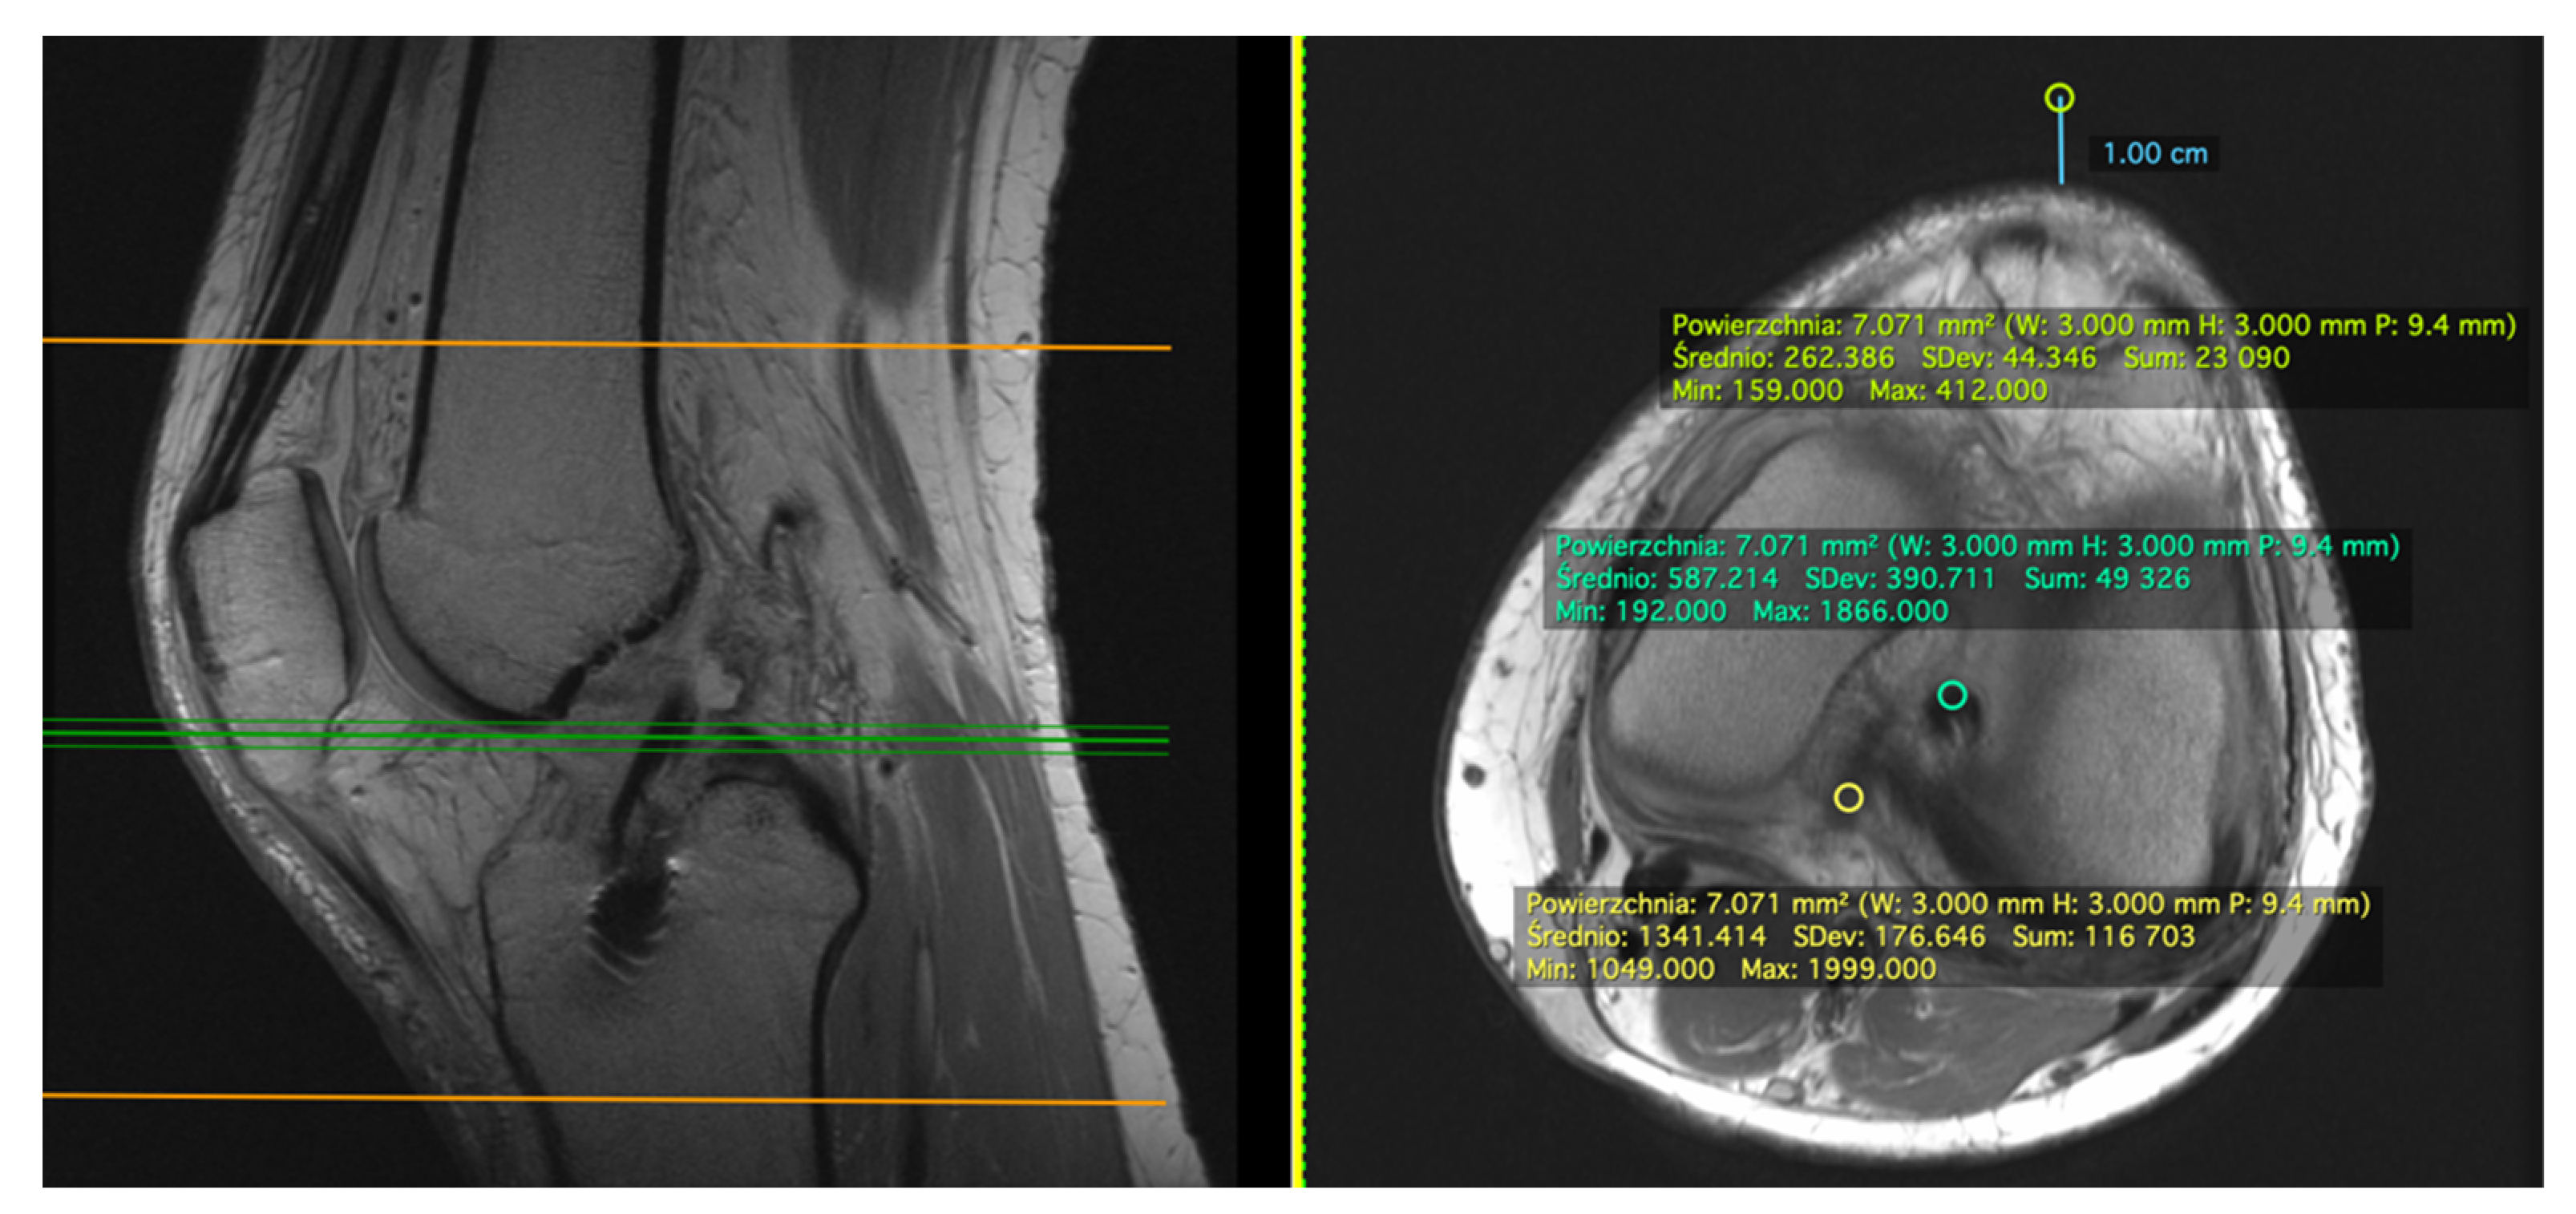

2.1. Measurement on the Sagittal Plane

2.2. Measurement on the Axial Plane

2.3. Standard Deviation (SD)